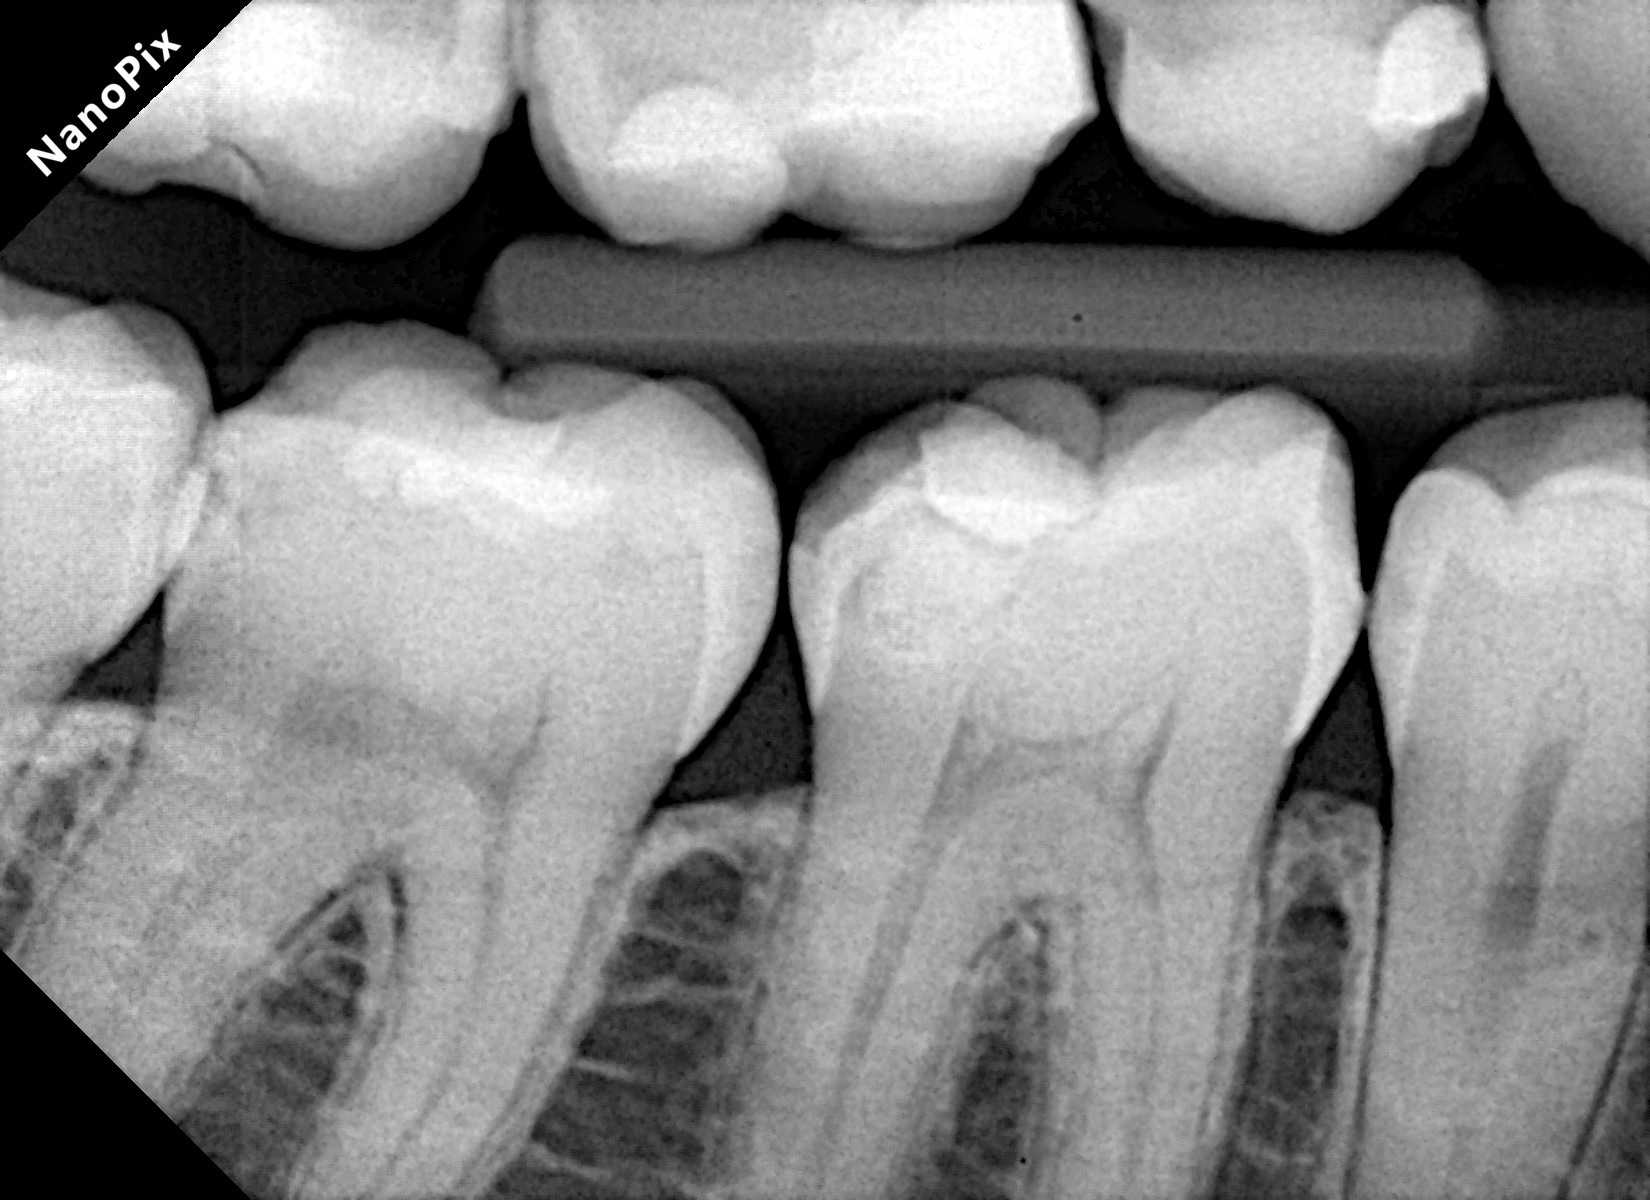

A 28-year-old woman presented to our office with complaints of sensitivity to cold temperatures and food impaction in her lower right quadrant. Her dental history revealed previous orthodontic treatment and multiple restoration failures in the same quadrant over the past 8-12 years.

Clinical examination showed significant mesio-occluso-distal (MOD) defects and Class 2 affecting teeth from #45 to #48.

Tooth #45: A distal carious lesion is suspected, potentially secondary to the adjacent mesial defect observed on tooth #46. No existing restoration is noted in this region, however, early discoloration and anatomical concavity suggest demineralization.

Tooth #46: Clinical examination revealed a mesial proximal carious defect with complete loss of the marginal ridge. On the distal aspect, an old composite restoration was observed, appearing underfilled and extended onto the occlusal surface. Evident marginal leakage and localized chipping were present along the restoration interface. Additionally, unsupported enamel was noted on the distobuccal cusp, indicating structural compromise and the risk of cusp fracture.

Tooth #47: An existing occlusal composite restoration demonstrated marginal discoloration and leakage. The distal surface exhibited a composite material of a different shade and texture, suggestive of a restoration placed at a later date. Lack of a defined marginal ridge resulted in an improper proximal contact. On the mesial surface, dark discoloration contiguous with the existing mesial pit composite indicated the presence of a recurrent or active Class II carious lesion.

Tooth #48: The mesial aspect showed dark discoloration extending into the existing mesial pit composite restoration, consistent with a developing or recurrent Class II carious lesion.

Bitewing radiograph confirmed the presence of multiple MOD / Class II carious lesions corresponding to the clinical findings. None of the defects demonstrated radiographic proximity to the pulp.

Figure 1. Multiple defects starting from tooth #45 to #48 as described above.Figure 2. Multiple class 2 defects starting from tooth #45 to #48 with loss of ideal contacts and contours.